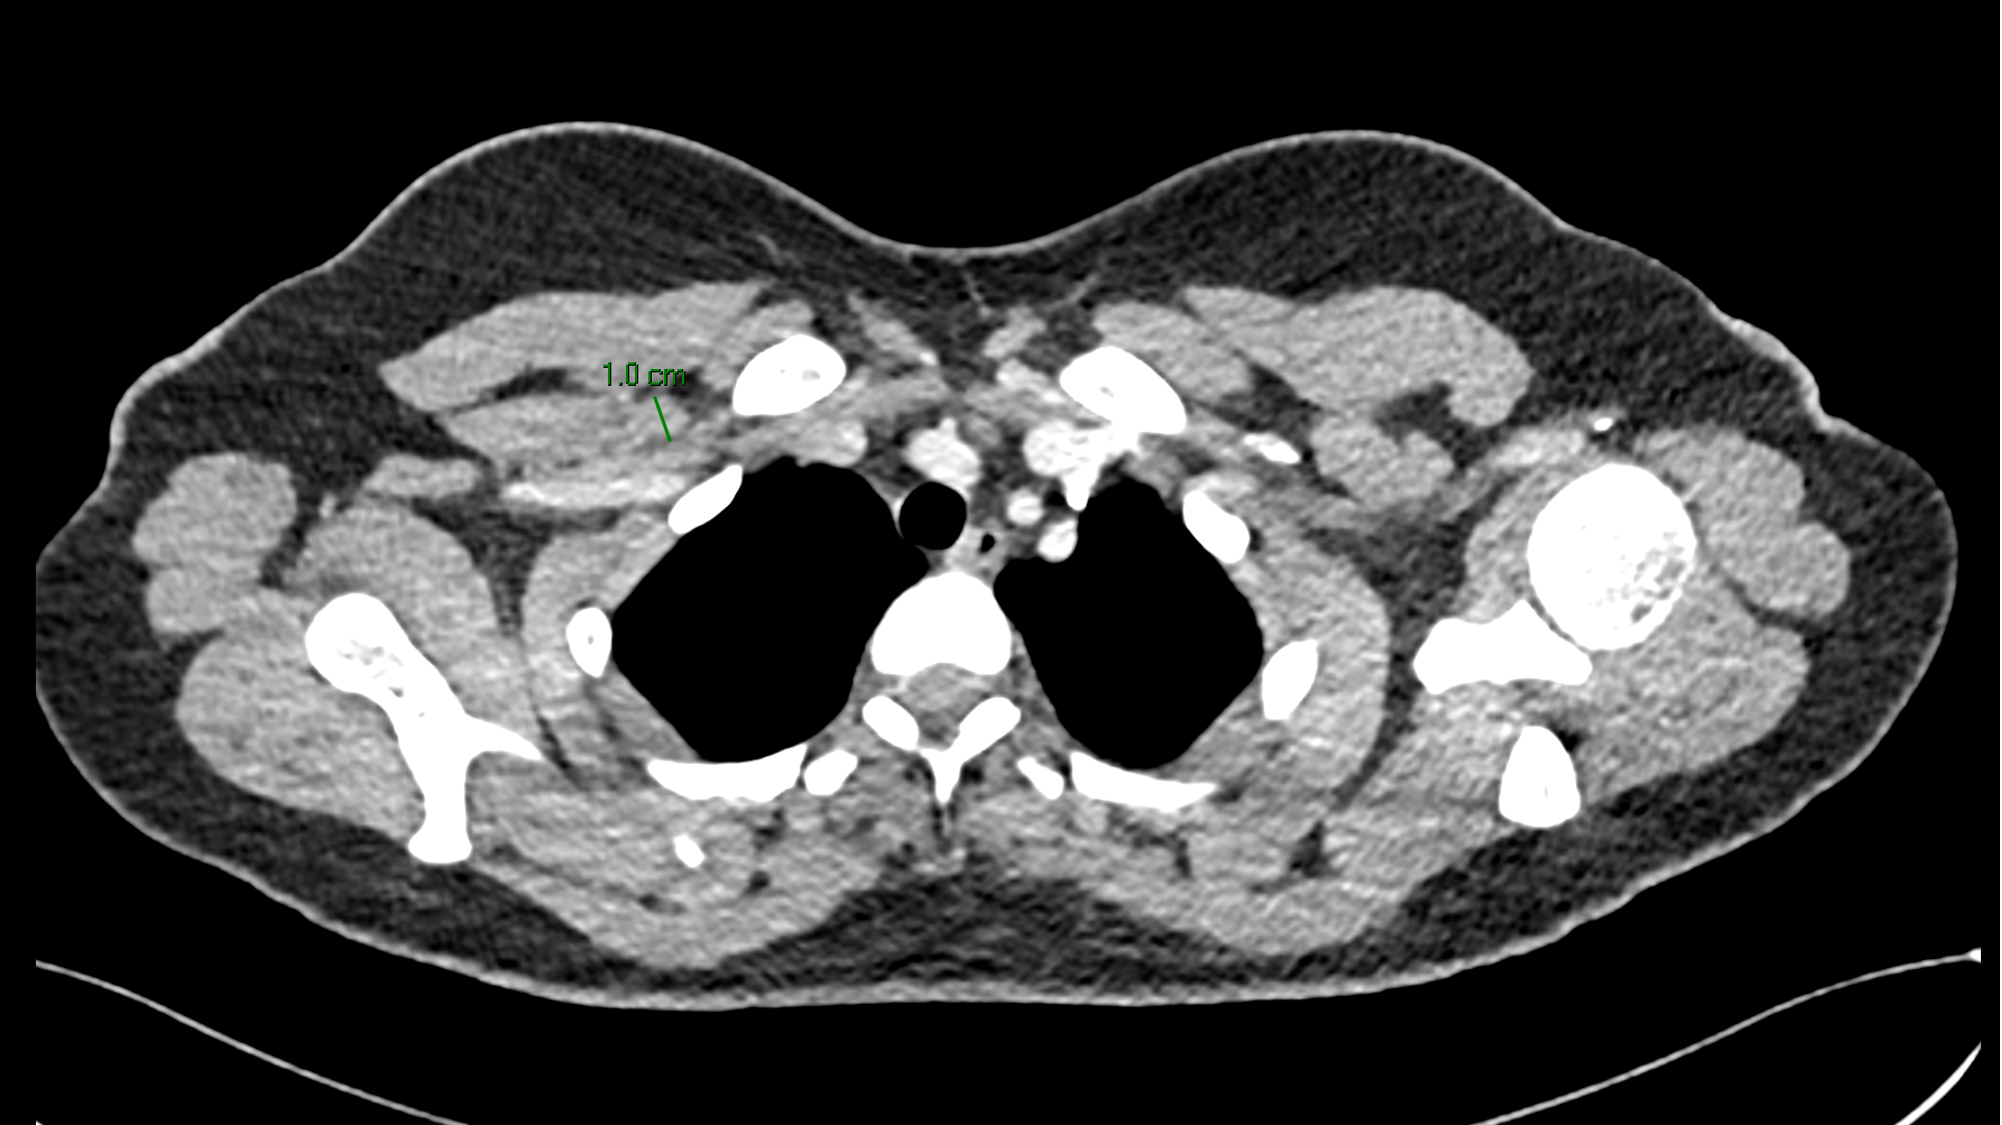

Imágenes de tomografía en adquisición axial en ventana para tejido blando, fase venosa, con su correspondiente correlación con imágenes de PET CT.

J, K Ganglio subclavio derecho con pérdida de su morfología e hilio graso, con eje corto de hasta 10 mm, con hipermetabolismo